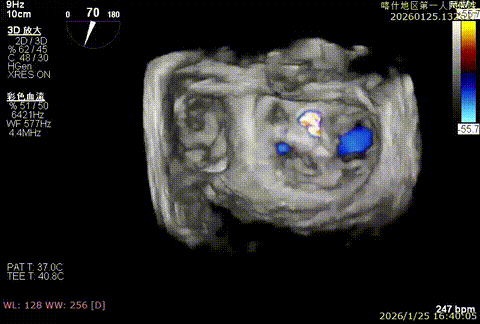

该例患者为VFMR,术前制定手术策略:患者二尖瓣重度反流,后叶严重栓系,心房心室扩大。患者瓣口面积4.5cm2,预计使用两枚XTR解决患者瓣叶脱垂和反流。考虑到先于2区进行钳夹,应该能获得足够的房间隔穿刺高度。术中经不断调整穿刺位点,最终穿刺高度4.4cm。成功穿刺后将第一枚XTR送入二尖瓣正上方,进行弹道测试Orientation调整后,最终定位于2区正上方下左心室。第一枚夹子在左室成功捕捞和钳夹瓣叶后,瓣叶反流程度显著降低,夹子外侧仍见部分反流,随后在第一枚夹子外侧再次放置一枚XTR,瓣叶反流程度进一步降低至微量。通过TEE观察,二尖瓣双孔组织桥稳定,跨瓣压差3mmHg,肺静脉逆流改善明显,手术安全结束。

3D enface观察反流

反流充分降低

术后压差3mmHg